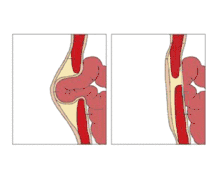

الفَتْق السُّرِّي (بالإنجليزية: Umbilical hernia) هو حالة صحية يحدث فيها تلف لجدار البطن وراء السرة، مما قد يتسبب في بروز السرة إلى الخارج. يتكون الانبعاج أو البروز من الدهون في منطقة البطن من الثرب الأكبر أو أحيانًا أجزاء من الأمعاء الدقيقة. في كثير من الأحيان يمكن أن يُضغط البروز مرة أخرى من خلال ثقب في جدار البطن، وربما ينبعج ثانيةً عند السعال أو أي تصرُّف يؤدي لزيادة الضغط داخل البطن. يكون العلاج جراحيًا، وقد تُؤدّى الجراحة من أجل الشكل التجميلي وكذلك الأسباب المتعلقة بالصحة.

يوجد الفتق في موقع السرة (تسمى عادة السرة، أو زر البطن) في الأطفال حديثي الولادة. على الرغم من أنه في بعض الأحيان، تميل هذه الفتوق إلى الشفاء دون أي تدخل علاجي في سن 2-3 سنوات.[2] نادرًا ما يحدث الانسداد والاختناق من الفتق لأن التلف الكامن في جدار البطن أكبر مما كان عليه في الفتق الإربي في الأطفال حديثي الولادة. ويرتبط حجم قاعدة النسيج الفتقي عكسيًا مع خطر الخنق (أي قاعدة ضيقة هي أكثر عرضة للخنق).

من المهم تمييز هذا النوع من الفتق السري عن الفتق المجاور للسرة، والذي يحدث في البالغين وينطوي على تلف في خط الوسط بالقرب من السرة، ومن قيلة سرية.